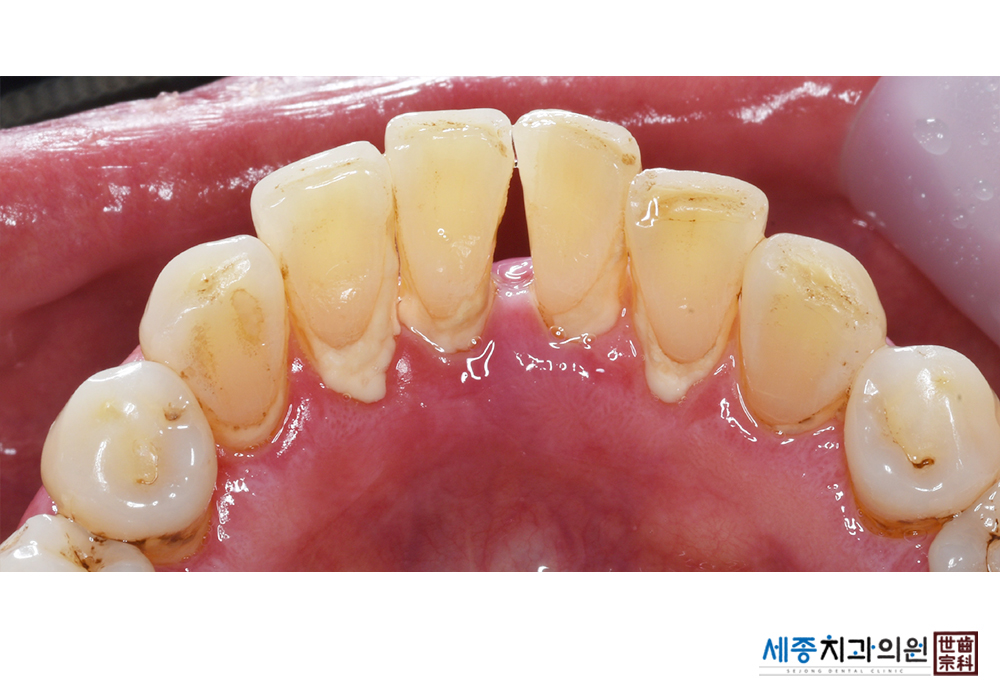

[스케일링] 치주질환 예방 스케일링

치료전 : 2023-01-05

치료후 : 2023-01-05

가글마취&저주파 스켈러를 사용한 스케일링